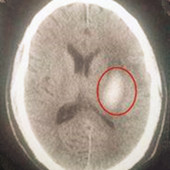

脳出血後遺症の治療前|脳出血後遺症の治療結果 治療前

脳出血後遺症の治療後|脳出血後遺症の治療結果 治療後